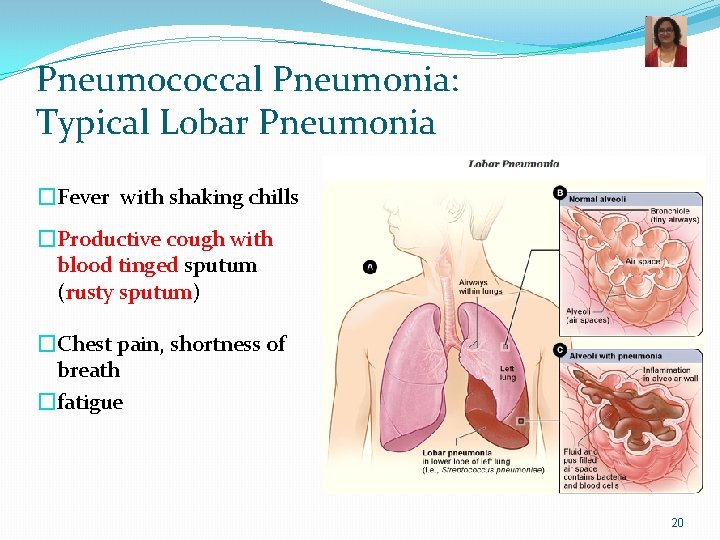

Pneumococcal Pneumonia: Typical Lobar Pneumonia �Fever with shaking chills �Productive cough with blood tinged sputum (rusty sputum) �Chest pain, shortness of breath �fatigue 20